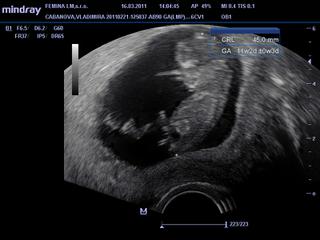

ahojte, uz som tu dlhsie nebola, ale ste sa rozpisali, trvalo mi kym som precitala tolko stran 🙂 ..vcera som bola na utz 11tt+1 podla PM, velkost dietatka podla utz je 11tt+2 cize 4,5cm od hlavicky po zadocek, som rada, ze malinke rastie tak ako ma, objednal ma na 24.3. na odbery krvi konecne, hadam mi uz da aj tehu knizku...na utz chodievam kazde 2tt, bola som uz 5x, v 9tt+6 a aj teraz sa poriadne hybalo hlavne na zaciatku utz, potom sa da do inej polohy a uz je v klude, teraz uz 1x sedelo, predtym stale bolo v polohe lah...nastastie som ani raz nevracala, ale chute mam poriadne, zatial som nepribrala co sa cudujem a hlavne ze nechudnem, uz teraz mam podvahu min. 8kg, tak to by bola katastrofa, keby som zle zvladala tehotenstvo, brusko mi nezacalo rast...uz sa neviem dockat kedy bude vidiet pohlavie dietatka, aj ked uz v pred dvoma tyzdnami lekar povedal, ze to vyzera na chlapca...ale kalendare vyzhadzaju na dievca...zahada? 🙂